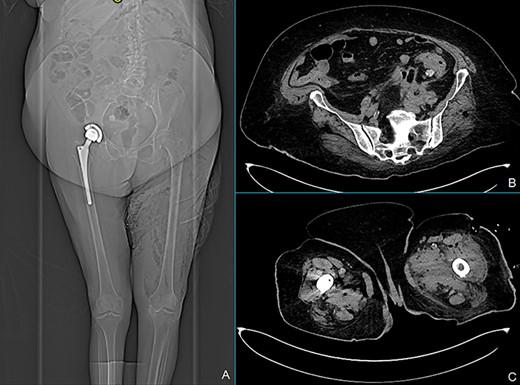

CT scan at the readmission: X-ray showed marked improvement of left leg emphysema (A), a decrease of pericolic abscess (B) and marked reduction of left leg collections (C).

We report a case of a 71-year-old woman with Class 3 obesity and Type 2 diabetes. The patient initially came to the emergency room for abdominal pain, fever (38.5°C) and swelling of the left lower limb. The blood tests showed a neutrophilic leukocytosis with white blood cells (WBC) 15 700 cells/mmc, neutrophils 13 800 cells/mmc, C-reactive protein (CRP) 303 mg/l and serum glucose 275 mg/dl. At the physical examination, the abdomen was soft with lower left quadrant tenderness, and the left lower limb was painful and warm with marked edema starting from the inguinal region. The patient was hemodynamically stable. Computed tomography (CT) scan of the abdomen extended to the lower limbs (Fig. 1) revealed the presence of air and fluid retroperitoneal collections, extending through the posterior abdominal wall muscles until the medial and anterolateral compartment of the left leg. Besides, thickening of the sigmoid wall with covered perforation was detected. Clinical and radiological findings were consistent with extensive gangrenous fasciitis possibly secondary to perforated diverticulitis. Wide-spectrum antibiotic therapy with meropenem and vancomycin was started and urgent fasciotomies were performed on the anterior, medial and lateral sides of the left leg. The patient was also treated with hyperbaric oxygen therapy and referred to the intensive care unit (ICU). A cultural test showed a polymicrobial infection of Klebsiella pneumoniae, Enterococcus faecalis and Candida albicans. Blood cultures were positives for Staphylococcus epidermidis. According to these findings, the antibiotic therapy was implemented by adding fluconazole and the hyperbaric therapy was stopped. The first postoperative course was uneventful. In postoperative Day (POD) 8, a CT scan showed a reduction of collections both in the retroperitoneum and in the left leg prompting the discharge of the patient from ICU. At that moment, we decided not to treat the diverticulitis surgically, according to the recent Consensus Statement of the European Association for Endoscopic Surgery and Society of American Gastrointestinal and Endoscopic Surgeons. In POD 16, since blood tests were completely normalized, physical examination of the abdomen was negative and surgical incisions were dry and clean, the patient was transferred to the rehabilitation unit. After 37 days from surgery, the patient was readmitted to our unit because of the occurrence of fever and the formation of a fistula at the site of the lateral fasciotomy producing fecal material (Fig. 2). The CT scan revealed marked improvement of abdominal and limb conditions, with a reduction of the pericolic abscess, collections and edema of the left leg (Fig. 3). Lab tests showed WBC 7800 cells/mmc, CRP 183 mg/l. Although CT scan findings showed improvement, the clinical evidence of colocutaneous fistula prompted us to surgery. Intraoperative findings confirmed acute diverticulitis with posterior covered perforation and retroperitoneal fistula. An enterocolic fistula was also detected. There was no contamination of the peritoneal cavity; so we performed sigmoid resection with primary mechanical end-to-end anastomoses without proximal diversion and ileal loop repair. Two drain tubes were placed both in the abdominal cavity and through the lateral fasciotomy. No early or late severe postoperative surgical complications were observed. In POD 4, the patient returned to normal bowel function and started oral refeeding. Abdominal and left leg drain tubes were respectively removed in PODs 5 and 7. An episode of fever (39.3°C) occurred in POD 9 and was attributed to candida infection and treated with antifungal therapy and central venous catheter removal. In POD 27, the patient was finally discharged in good clinical condition with normal lab tests and left leg wound re-epithelialization.